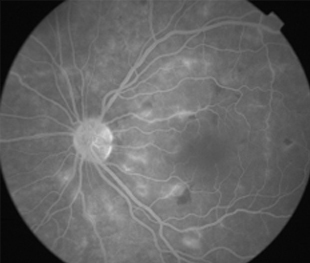

Angiografía OD

2 meses: disminución de manchas algodonosas y hemorragias con mejoría de circulación

- Bilateral, 20/200 a CD, alteración de la capa de fibras nerviosas, atrofía disco óptico.

- Angiografía: teñido arterial, escape capilar, más tardíamente, no perfusion arteriolar y venular con teñido de las paredes vasculares y dilatación venosa.